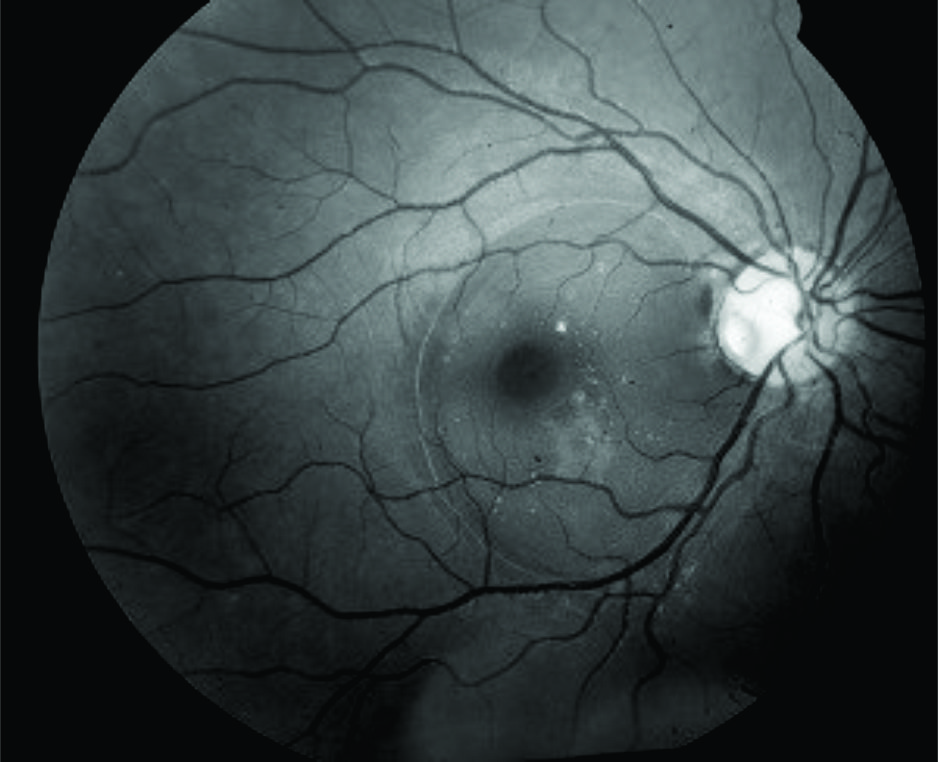

Optic disc pit is a congenital anomaly of the optic nerve frequently associated with macula detachment. It has a poor visual prognosis if left untreated. The treatment of the optic disc remains controversial and includes the use of laser along the edge of the optic nerve, vitrectomy with gas tamponade with or without removal of posterior hyaloid. We report a case of a 19-year-old female with a longstanding macula detachment due to optic disc pit who was treated with vitrectomy with removal of posterior hyaloid, gas tamponade, and laser. Despite longstanding macular detachment the final visual acuity was 20/25.